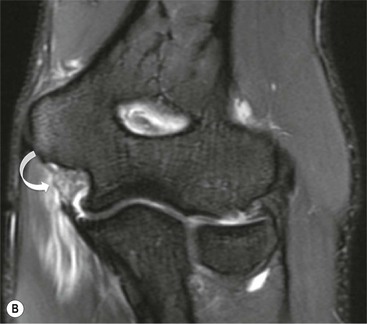

The scapholunate ligament is most frequently involved. Radiographs may show scapholunate diastasis (>3 mm). The lunate demonstrates dorsal rotation on lateral views and volar rotation of the scaphoid. This results in an increase in the scapholunate angle (>60°) known as dorsal intercalated segment instability (DISI) (Fig. 46-27). A DISI deformity of the carpus may also be associated with fractures of the scaphoid.

Abnormal communication between the radiocarpal and midcarpal joints may be seen on arthrography (Fig. 46-28), which is usually combined with MRI or CT16 (Figs. 46-29 and 46-30). However, direct visualisation of the ligaments is possible with conventional MRI. The most important features to describe that help determine management include the following: